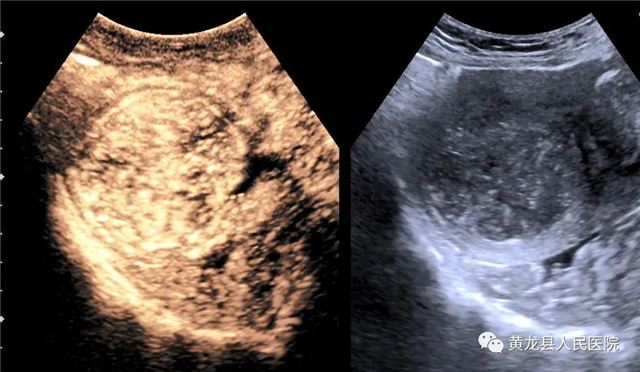

子宫肌瘤术前造影

子宫肌瘤术后造影